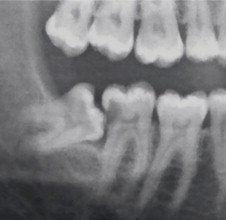

위 엑스레이 사진도 첫번째 사진과 마찬가지로 사랑니에 의해서 앞 치아에 충치가 생긴 걸 보여줍니다. 사랑니가 있는 경우 앞치아의 칫솔질 관리가 잘 되지 않는 경우가 많습니다. 구조가 칫솔질이 잘 닿지 못하거든요. 그래서 충치가 잘 생깁니다. (출처: https://www.sciencedirect.com/science/article/abs/pii/S0266435613004877)